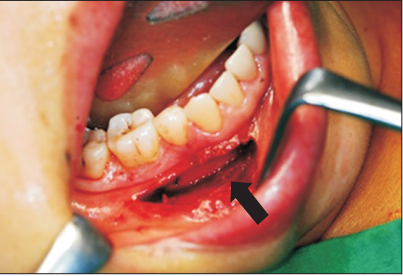

由于肿块靠近颏孔,术中需要精细解剖,以确保最小的神经损伤。

口腔脂肪瘤在临床中实属罕见,通常无症状,生长缓慢,手术切除为主要的治疗手段。由于病例中脂肪瘤的位置靠近重要的解剖结构,术中一定要注意 保护好周围的神经,以免造成神经损伤。 doi.org/10.5125/jkaoms.2015.41.4.213